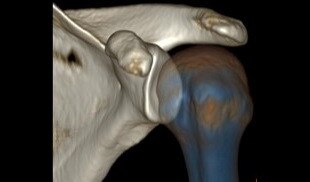

Kas-İskelet Görüntü Galerisi